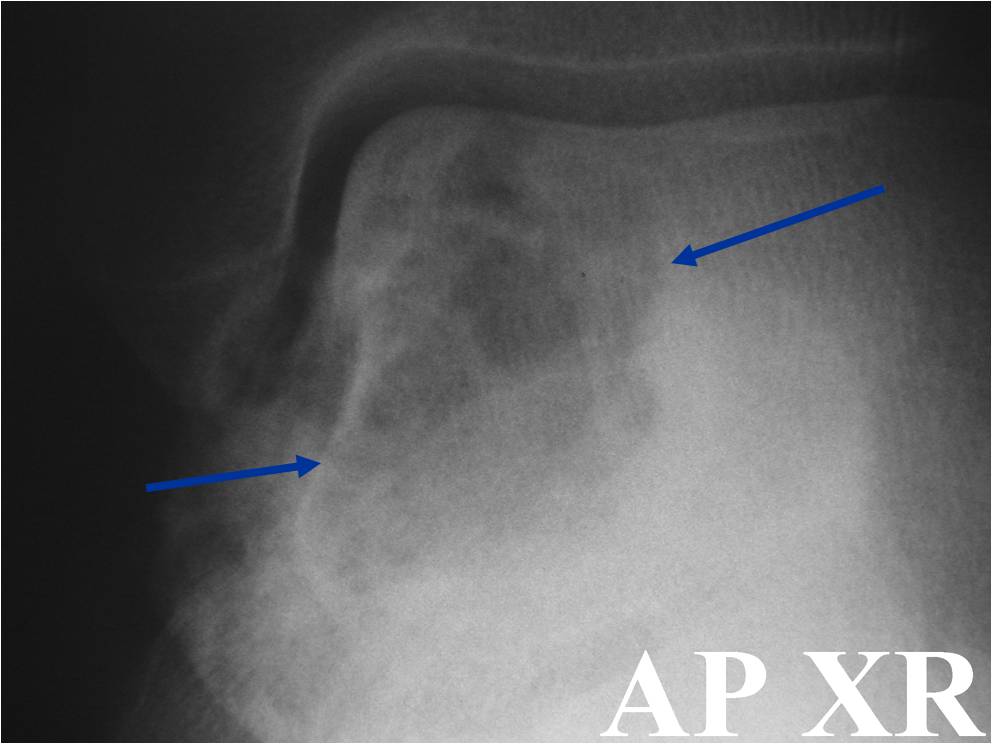

Radiographic Presentation

- Presents as a highly defined/well circumscribed geographic oval/round lytic defect

- Surrounded by rim of sclerotic bone

- Usually in epiphyseal region

- (Plain x-ray appearance)

- Geographic lytic lesion IA/IB margin of sclerosis

- Usually Eccentric more often than Central in the bone

- Rarely expansile (rarely penetrates the cortex)

- Calcified chondroid matrix 30%-50% of cases

- Often better detected with a CT Scan

- Periosteal Reaction 30-50% of cases

- Usually occurs in Adjacent Diaphysis/Metaphysis since epiphysis is intraarticular and not surrounded by periosteum

- (CT appearance)

- Most useful for detecting subtle mineralization not apparent on X-rays

- Useful for identifying intact periosteum around any expansile soft tissue component

- surrounding thin reactive shell of bone/mineralization (Egg Shell Rim of Calcification)

- helps place the tumor in a benign category

- helps evaluate:

- bony quality

- extent of bone and cortical destruction

- whether the subchondral plate of bone adjacent to the articular cartilage has been destroyed or is intact